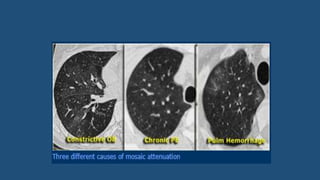

Mosaic attenuation

• Used to describe density differences between affected and non-affected lung

areas.

• There are patchy areas of black and white lung.

• The role of the radiologist is to determine which part is abnormal: the black or

the white lung.

• When ground glass opacity presents as mosaic attenuation consider:

• Infiltrative process adjacent to normal lung

• Normal lung appearing relatively dense adjacent to lung with air-trapping

• Hyperperfused lung adjacent to oligemic lung due to chronic thromboembolic disease

Cont..

• There are two diagnostic hints for further differentiation:

• Look at expiratory scans for air trapping

• Look at the vessels

• If the vesses are difficult to see in the 'black' lung as compared to the

'white' lung, than it is likely that the 'black' lung is abnormal.

• Then there are two possibilities: obstructive bronchiolitis or chronic PE.

• Sometimes these can be differentiated with an expiratory scan.

• If the vessels are the same in the 'black' lung and 'white' lung, then we are

looking at a patient with infiltrative lung disease e.g. pulmonary h’ge.